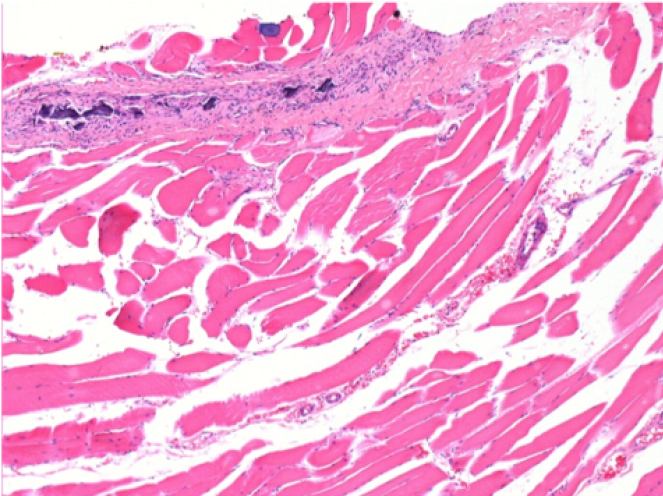

3 months (D90)after Endopeel Injection 0.1ml in the right pretibial muscle.

0.5 ml ( 5x 0.1ml) Endopeel SC Injection in the right subcutaneous pretibial area.

L:200x-Control-SC

R-D10-SC-200X